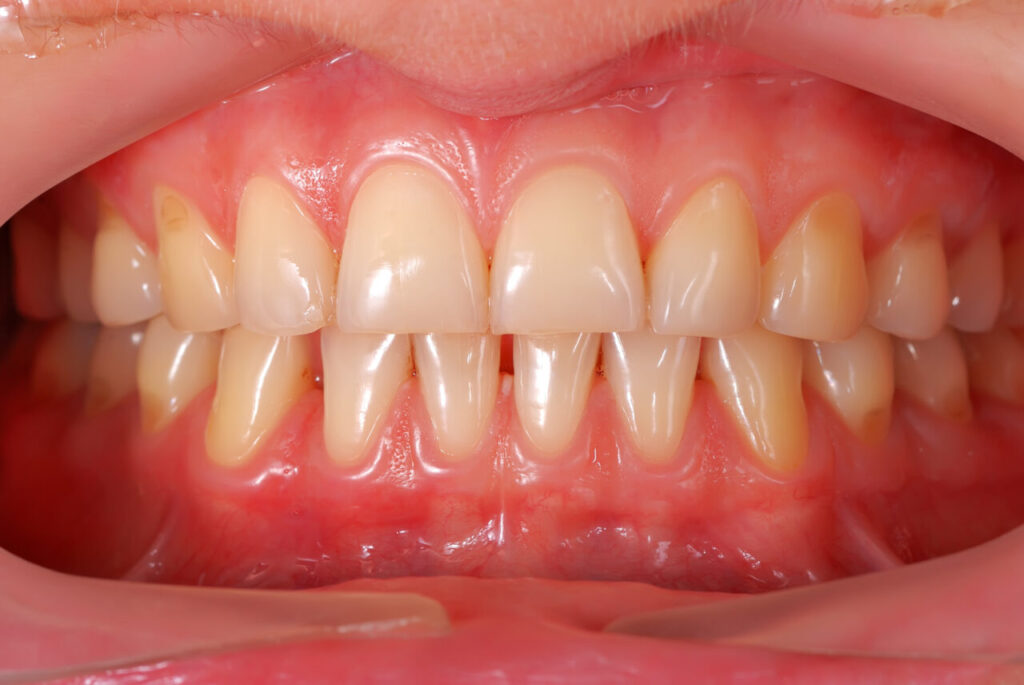

②歯が長く見える・歯肉が多く覆っている(歯冠長不足)

本来の歯の長さより歯ぐきが多く被ってしまい、短い歯に見えている状態。

歯肉を少し整えるだけで印象が大きく変わる「歯肉整形術」が有効です。

歯肉整形術

歯ぐきが歯を覆いすぎている場合に行う、歯肉をきれいに整える処置。

歯本来の長さがしっかり見えるようになり、歯ぐきの露出が自然な範囲に近づきます。

歯周外科を行うクリニックで施術します。